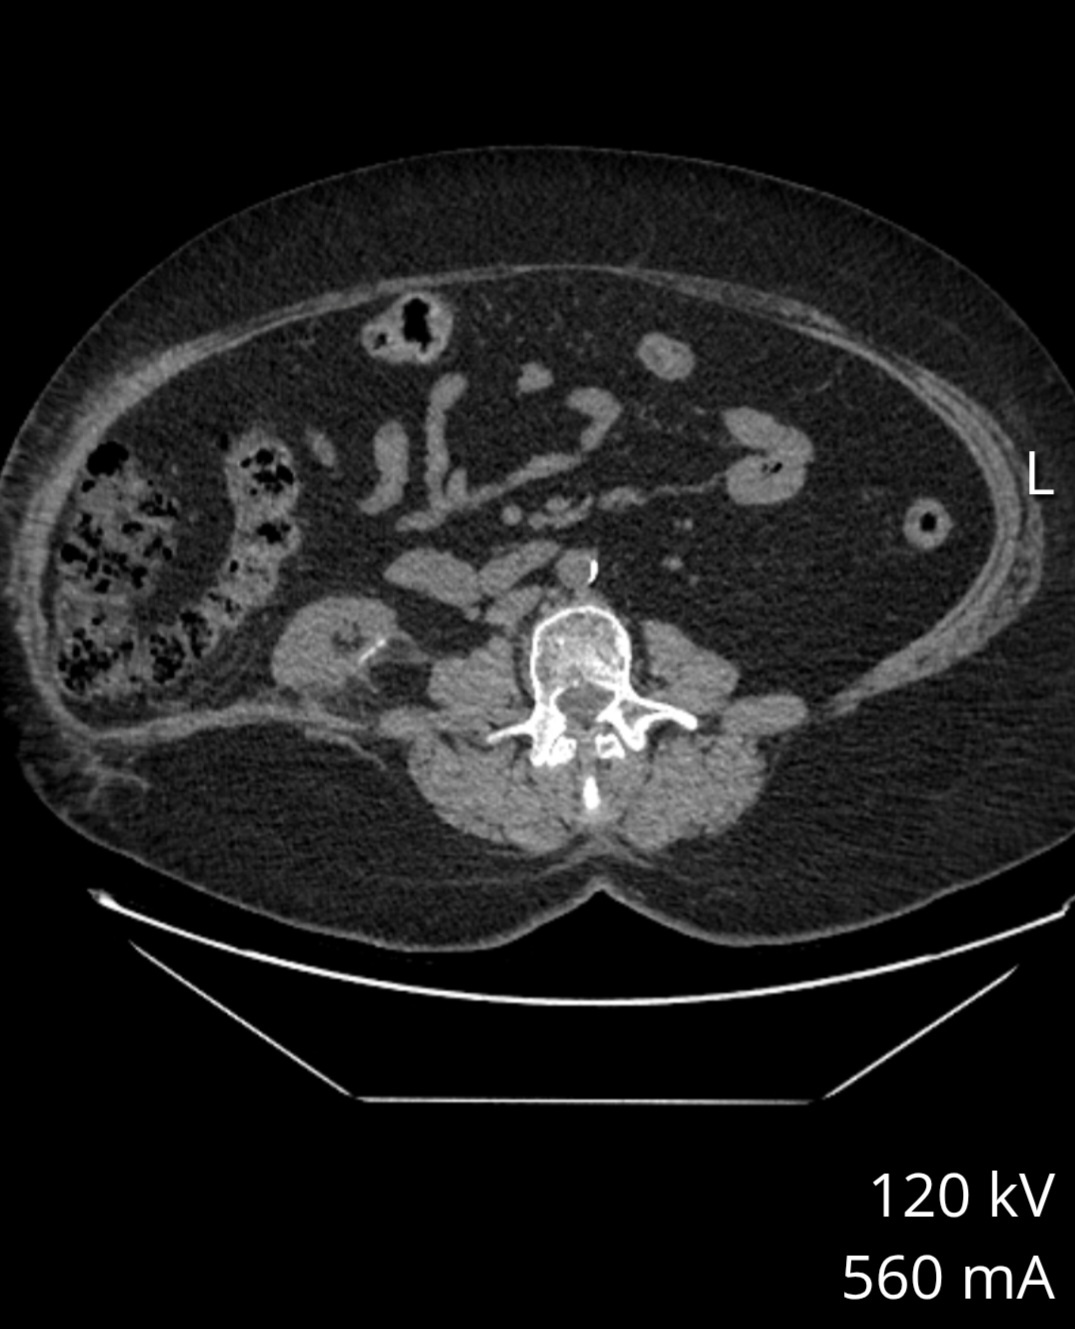

When I asked a specialist in hernias he said it would make it worse. And that mesh wouldn't fix it. I have read of them attaching mesh to rib and hip but then creates mobility issues. I don't see why I can't rebuild the muscles they cut. We're did they attach your mesh? Had your intestines move out of place? Did you ct ever look like this?